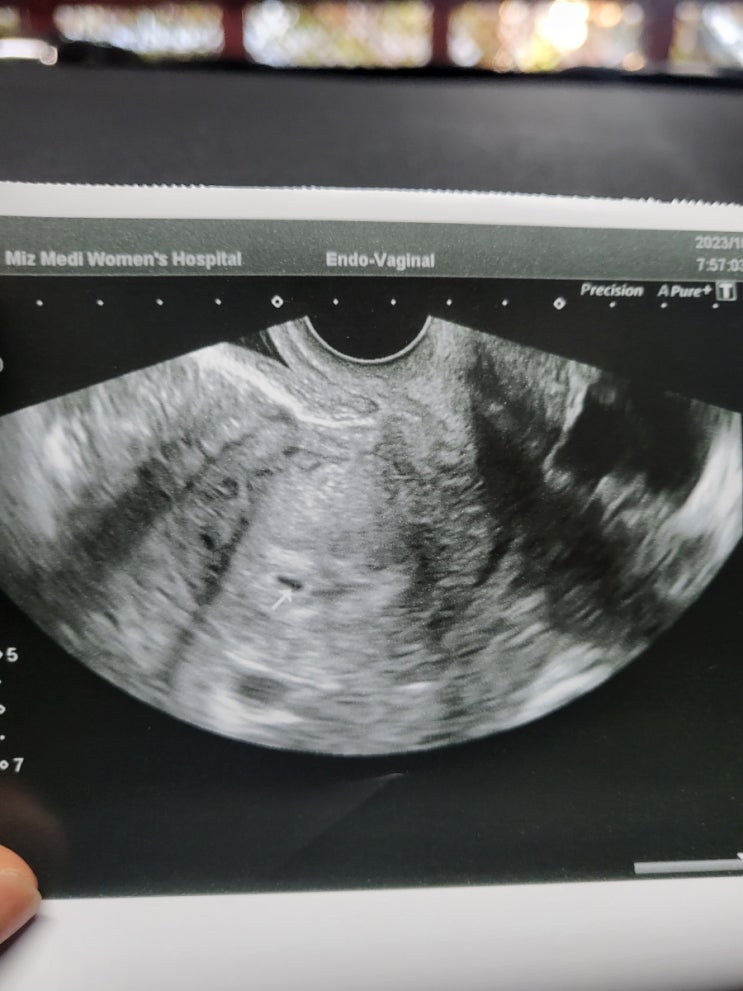

[임신준비] 강서미즈메디: 산전검사 및 나팔관조영술 통증, 시기, 비용

강서미즈메디: 나팔관조영술 직후 임신->현재 임신32주차 [임신준비] 강서미즈메디: 산전검사 및 나팔관...